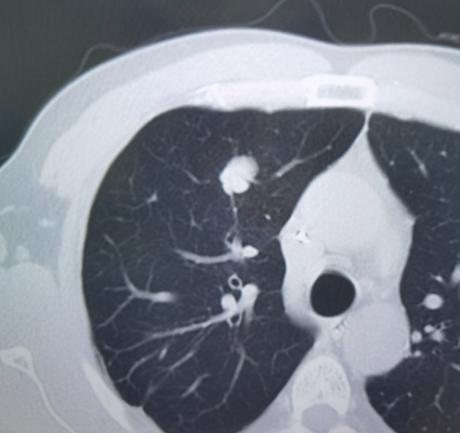

今天听到一个噩耗。揪心的痛! 一个同事,才33岁,连续几天午睡后不停的打嗝,没太在意,昨天晚上突然面部手脚发麻,紧接着就跌倒晕了过去,送到医院确诊为急性脑梗死。虽然立刻进行了手术,但最终还是没能抢救回来。 后来才知道,同事每次打完嗝,其实都有一点中风的前兆,但都没有引起他的重视,以为是工作太劳累了,如果当时立即去医院,也许就能挽回一条生命。 他就这样突然走了,留下老婆和两个不满10岁的儿女。每个月还有6000的房贷,以后怎么生活?我不敢细想。 很多人不知道,持续打嗝确实是脑梗死的非典型前兆之一。临床数据显示,约有5%的缺血性脑卒中患者,发病前会出现顽固性呃逆症状,这是因为脑血管堵塞压迫到了控制膈肌运动的神经中枢。这种症状很容易被当成劳累、肠胃不适,从而错过黄金救治时间。 33岁的年纪本不该和脑梗死挂钩,但现在中青年患病的案例越来越多。相关调查显示,我国45岁以下的脑卒中患者占比已经达到15%左右,长期熬夜、高油高盐饮食、缺乏运动、过度劳累都是主要诱因。这位同事平时就是公司的加班常客,经常忙到后半夜才回家,身体早就发出了预警信号。 上有老下有小的年纪,倒下的从来不是一个人,而是一个家庭。6000元的房贷每月雷打不动,两个孩子的教育开支逐年递增,失去顶梁柱的家庭瞬间陷入困境。身边不少人都在透支健康换收入,总觉得年轻就是资本,却忘了身体的承受能力有上限。 脑卒中的年轻化趋势,给所有职场人敲响了警钟。身体的小信号从来不是小事,不要用“太累了”“忍忍就好”敷衍自己。健康不是透支的筹码,而是支撑家庭的基石。多关注身体的预警,定期体检,规律作息,才是对自己和家人最大的负责。